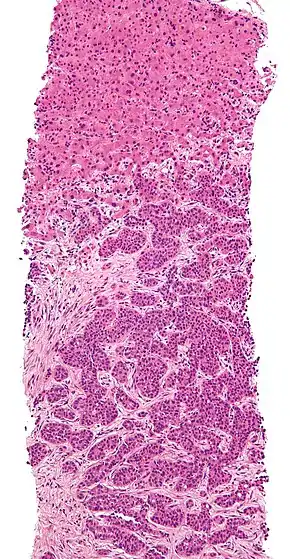

Lymph node with almost complete replacement by metastatic melanoma. The brown pigment is focal deposition of melanin